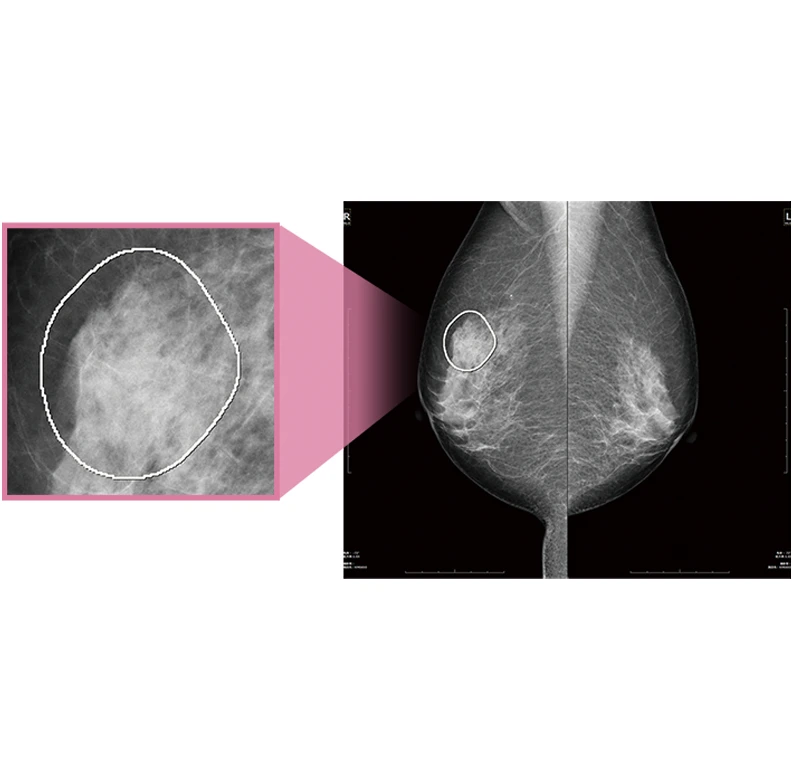

6. 乳がんの早期発見から治療まで Women’s Health

『FINO.VITA.GX typeMG』はマンモグラフィ診断に最適なワークフローを実現し、乳腺領域に特化した充実機能を搭載した専用ビューワーです。乳腺専用レポーティングシステムやマンモグラフィ診断支援CAD『MGCAD-i』もラインナップし、効率的な診断をサポートします。さらに乳房構成解析ソフトウェア『Breast Density Assessment(Bda)』は乳房構成を定量的に判定。ブレストアウェアネスの促進、そして、一人ひとりにとってよりよい乳がん検診を提案します。